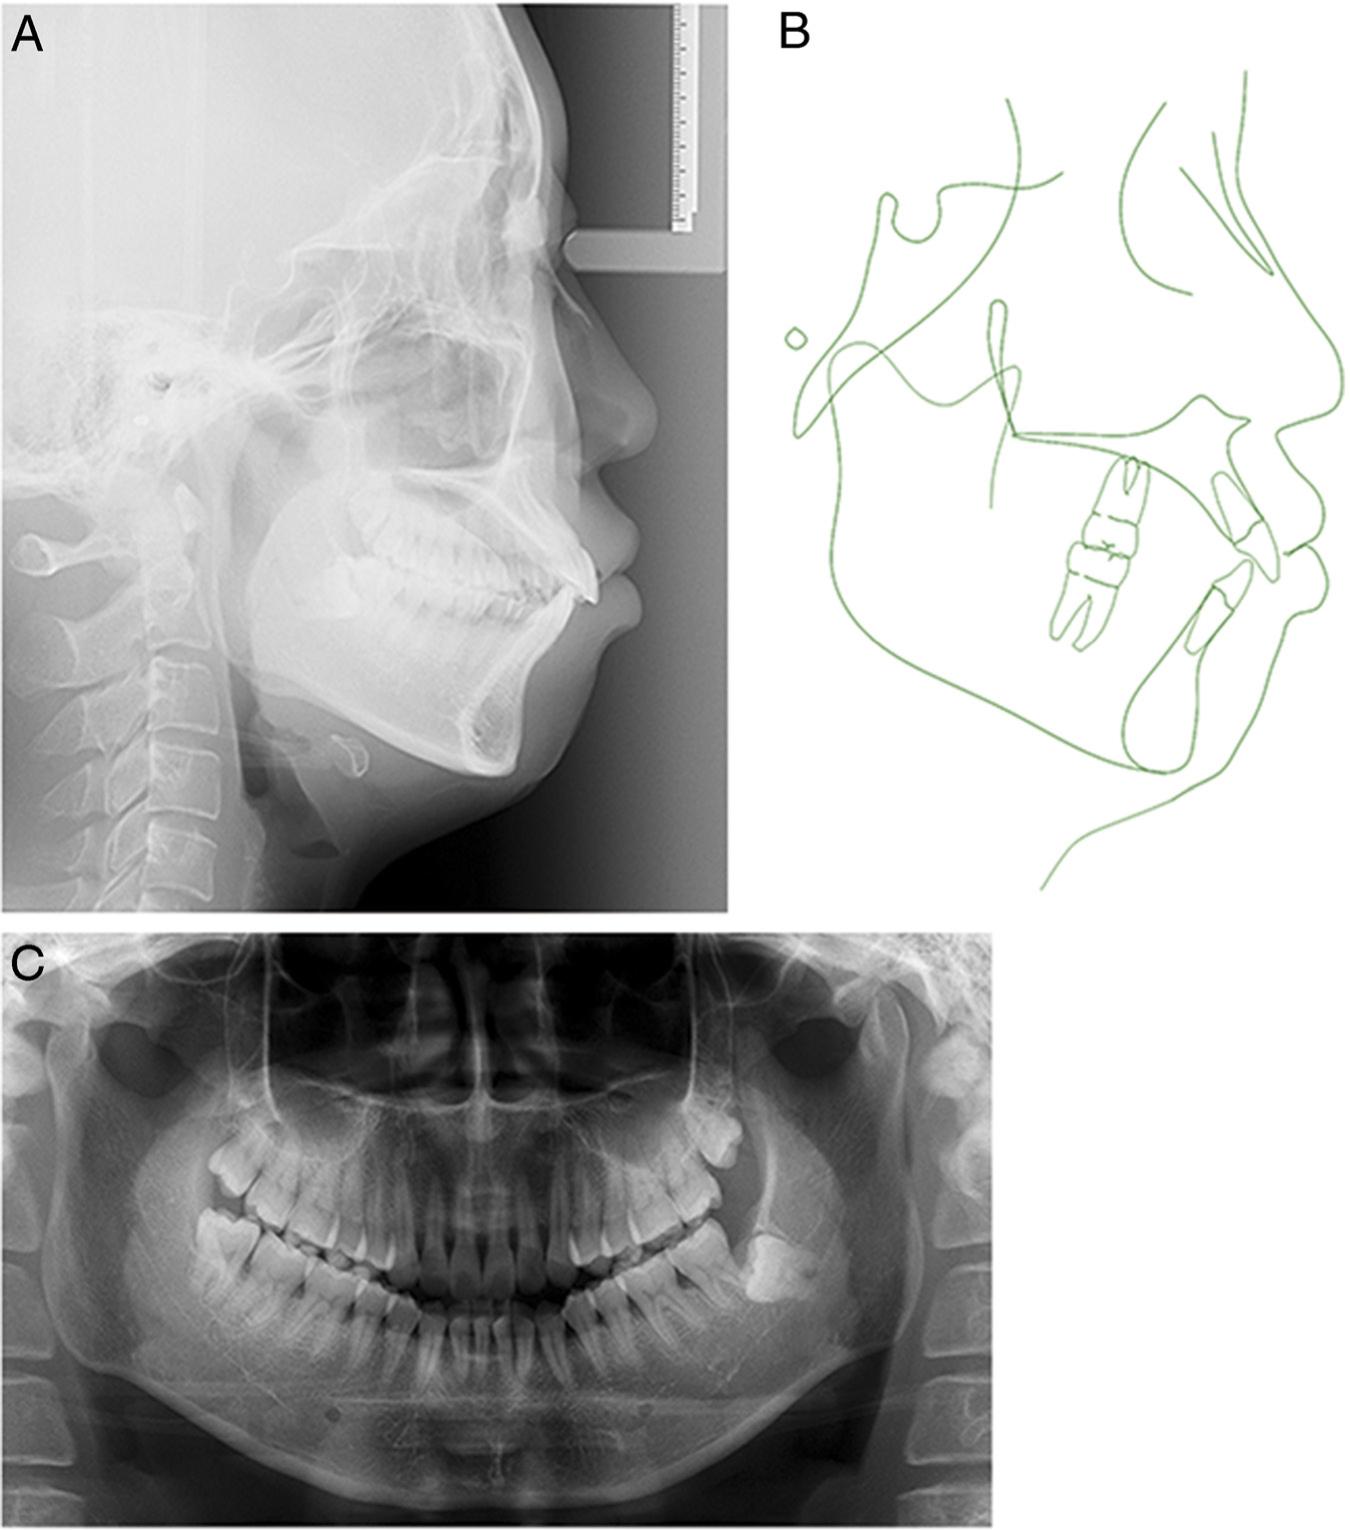

Figure 3.

Pretreatment radiographs and tracing: (A) lateral cephalometric radiograph; (B) cephalometric tracing; and (C) panoramic radiograph.

The panoramic radiographic findings revealed that the left mandibular third molar was horizontally impacted (Figure 3). A lateral cephalometric analysis showed a skeletal Class I pattern (ANB, 4.3°), a hyperdivergent growth pattern (FMA, 29.0°; GoGn-SN, 38.2°), and maxillary anterior tooth extrusion (PP-U1, 34.3 mm). The maxillary (U1-NA, 8.5 mm/32.2°) and mandibular incisors (L1-NB, 8.0 mm/31.0°; U1-L1, 118.1°) protruded. The soft tissue findings confirmed that the upper and lower lips were protrusive (the upper lip to E-line, 3.0 mm; lower lip to E-line, 7.0 mm) with an acute nasolabial angle (NLA, 77.0°) (Table I).